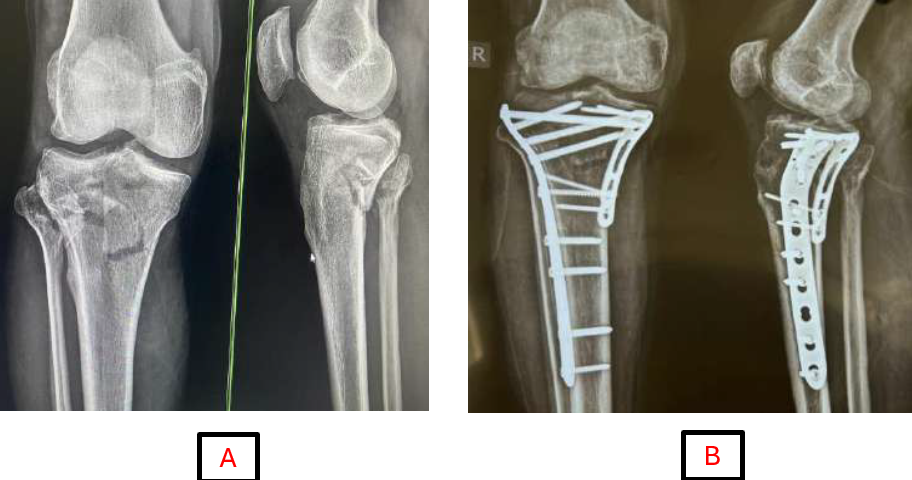

The mean range of motion at the final follow-up was recorded at 125° with a standard deviation of 9.90°. A significant improvement in range of motion was noted between the first and second follow-ups, followed by a gradual enhancement in subsequent assessments. All patients achieved a range of motion exceeding 90° during the final evaluation. Fractures categorized as Schatzker types II and III were treated with a single LCP (Fig. 1), while dual plating was required for nearly all cases of types V and VI (Fig. 2). In addition, three cases of type IV fractures were fixed with dual plating, and one type V fracture was stabilized utilizing triple plating.

Figure 2: (a and b) Pre-operative and 6-month follow-up radiograph of Schatzker type VI proximal tibia fracture.